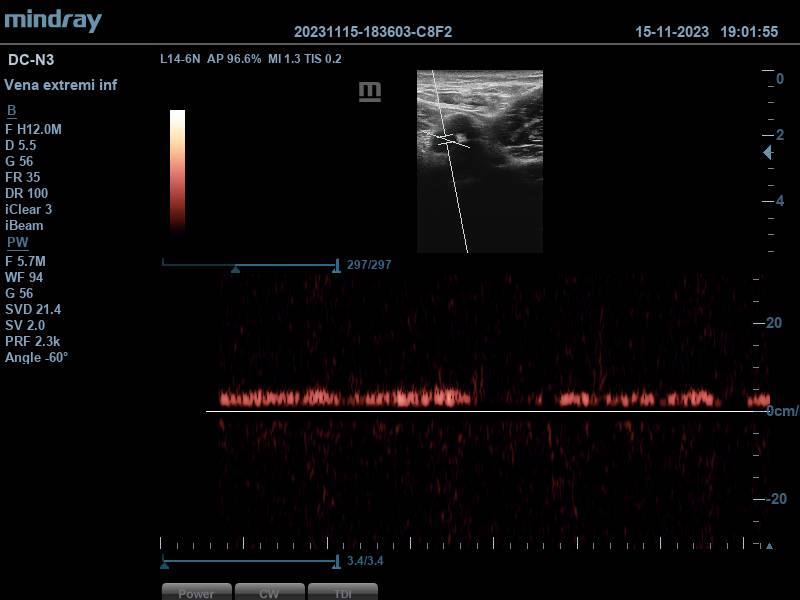

Se aplica Doppler pulsado, obteniéndose dos espectros compatibles con vasos arteriales (correspondientes a la arteria femoral superficial y femoral profunda), y otros dos espectros con patrón sugestivo de flujo venoso, que aumenta con la compresión del gemelo, generando picos de flujo. Todo ello, hace pensar en que estamos ante una duplicidad femoral.